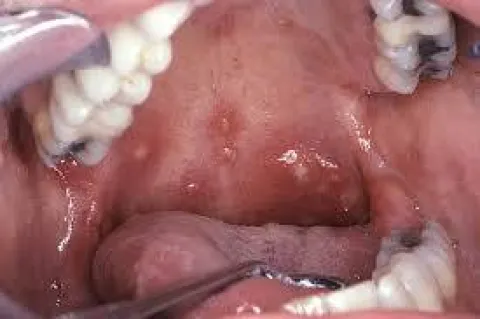

Choroba jamy ustnej zdjęcia

Jama ustna choroba bostonka

Choroba bostonka owrzodzenie jamy ustnej

Owrzodzenie jamy ustnej bostonka

owrzodzenie jamy ustnej